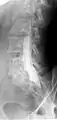

Conventional myelography in oblique projection. You can see the individual nerve root sheaths.